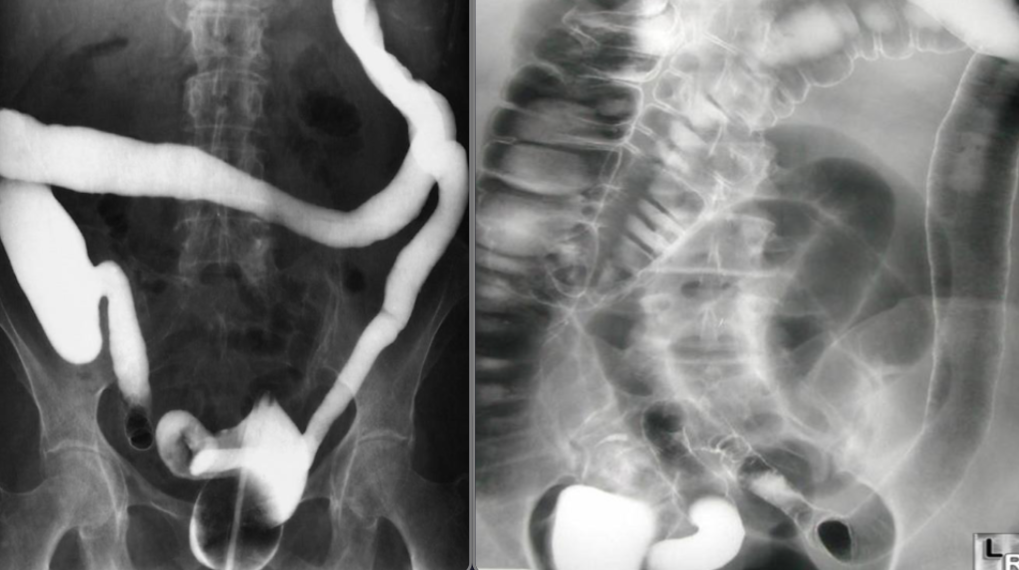

Single & Double (rt) contrast barium enema

- The haustra are lost and the colon becomes narrowed and shortened, coming to resemble a rigid tube.

- Narrowing and shortening of colon Feature less colon give lead pipe appearances

Abdominal pain and diarrhea

Imaging examination Diverticulosis - Double-contrast barium enema of the colon

Findings or description Multiple diverticula in the colon can be seen (examples circled in green).

Diagnosis Diverticulosis

Target sign in intussusception

Ultrasound abdomen (bowel; transverse plane)

Concentric alternating hyperechoic and hypoechoic rings are visible.. Together the alternating

layers produce a target-like appearance (target sign)